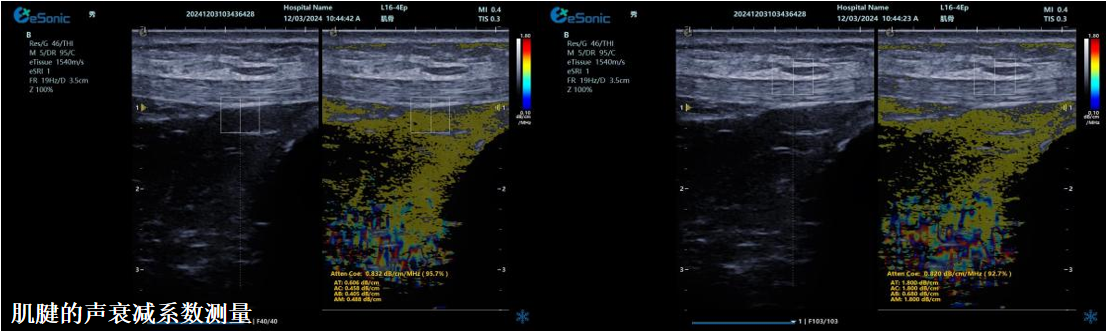

ATI高级声衰减成像

Ø独有的幅度损失的衰减方法ALA,准确性高,稳定性好,实时性好Ø业界唯一支持凸阵与线阵两种探头Ø支持多个取样框Ø提供两种显示单位

肌骨领域的应用

Ø肌腱炎症或损伤的评估Ø肌肉拉伤的定位Ø关节磨损或炎症的诊断Ø骨质疏松的早期发现和监测